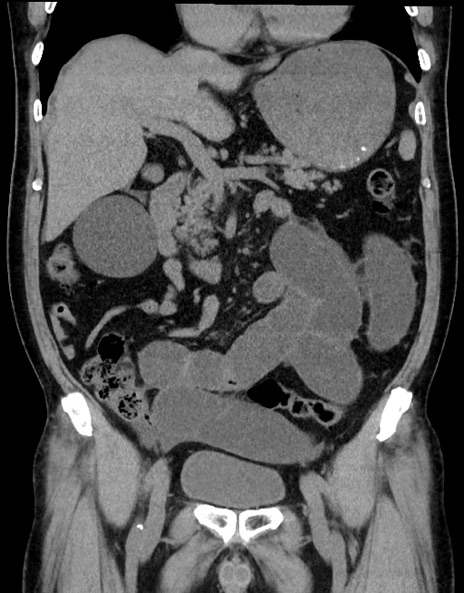

症例15(冠状断像)

【症例】70歳代男性

【主訴】腹痛

【現病歴】今朝から腹痛あり。全体的に痛い。特に左上の方。排ガスが今日はない。冷や汗が出る。

【既往歴】直腸癌術後

【身体所見】左側腹部〜上腹部に圧痛あり。腹膜刺激症状明らかなではない。軽度反跳痛。左下腹部に術後瘢痕あり。

【データ】WBC 7700、CRP 0.02